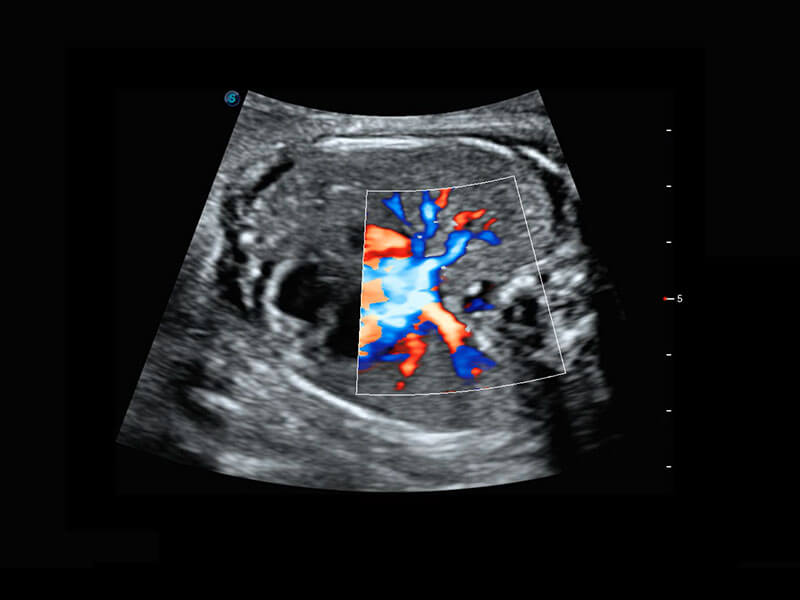

• 四腔心血流

• 右室双出口

P60搭载宽频带线阵探头、宽景成像、弹性成像技术,为您提供乳腺应用方案。P60支持高频相控阵探头、线阵探头、腹部高频探头、腹部微凸探头等,丰富的探头群搭载敏感的彩色血流成像,适用于新生儿多种脏器检测要求,满足新生儿筛查需求。

• 新生儿肝血管癌